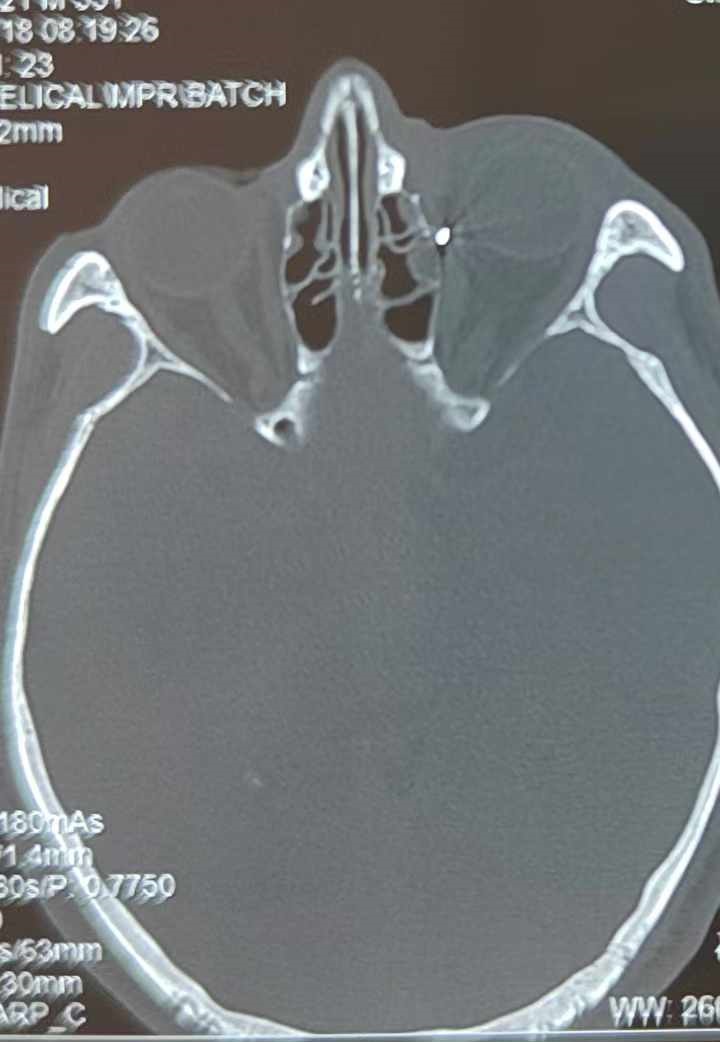

裝修工人高先生在作業(yè)過程中不慎被砸傷左眼,送至廈門眼科中心救治時,眼外傷及眼底病2科副主任醫(yī)師李海波博士在CT檢查報告中發(fā)現(xiàn),進入眼內(nèi)的異物在眶尖極為隱匿的位置,想要“不動聲色”地取出來,有些難度。

從CT報告中可以看出,高先生眼內(nèi)的異物不是很大,但位于眼窩深處,緊鄰鼻骨,從CT影像判斷應該是金屬或合金異物。一般臨床上遇到這樣的情況,醫(yī)生會建議“保守觀察”,若異物傷及神經(jīng)、發(fā)生炎癥感染等,則需到條件較好、有眼眶病和眼外傷專業(yè)醫(yī)師的醫(yī)院進行二期眶內(nèi)異物取出術(2021年《中國眼眶異物診斷和治療專家共識》)。